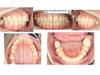

Зубные ряды

Резцовое перекрытие 1/3,

Кривые Шпее: верхняя – прямая, нижняя – глубокая

Центральные линии симметричны